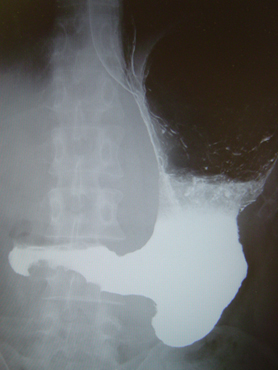

(b)胃X線検査

- 硫酸バリウムとガスを発生する発泡剤を服用してX線で撮影することにより胃の内側の変化をとらえます。胃全体の形や動きが分かり、がんの範囲を決めるのに重要な検査です。内視鏡検査に比べて侵襲が少ないため、胃がん検診によく用いられます。